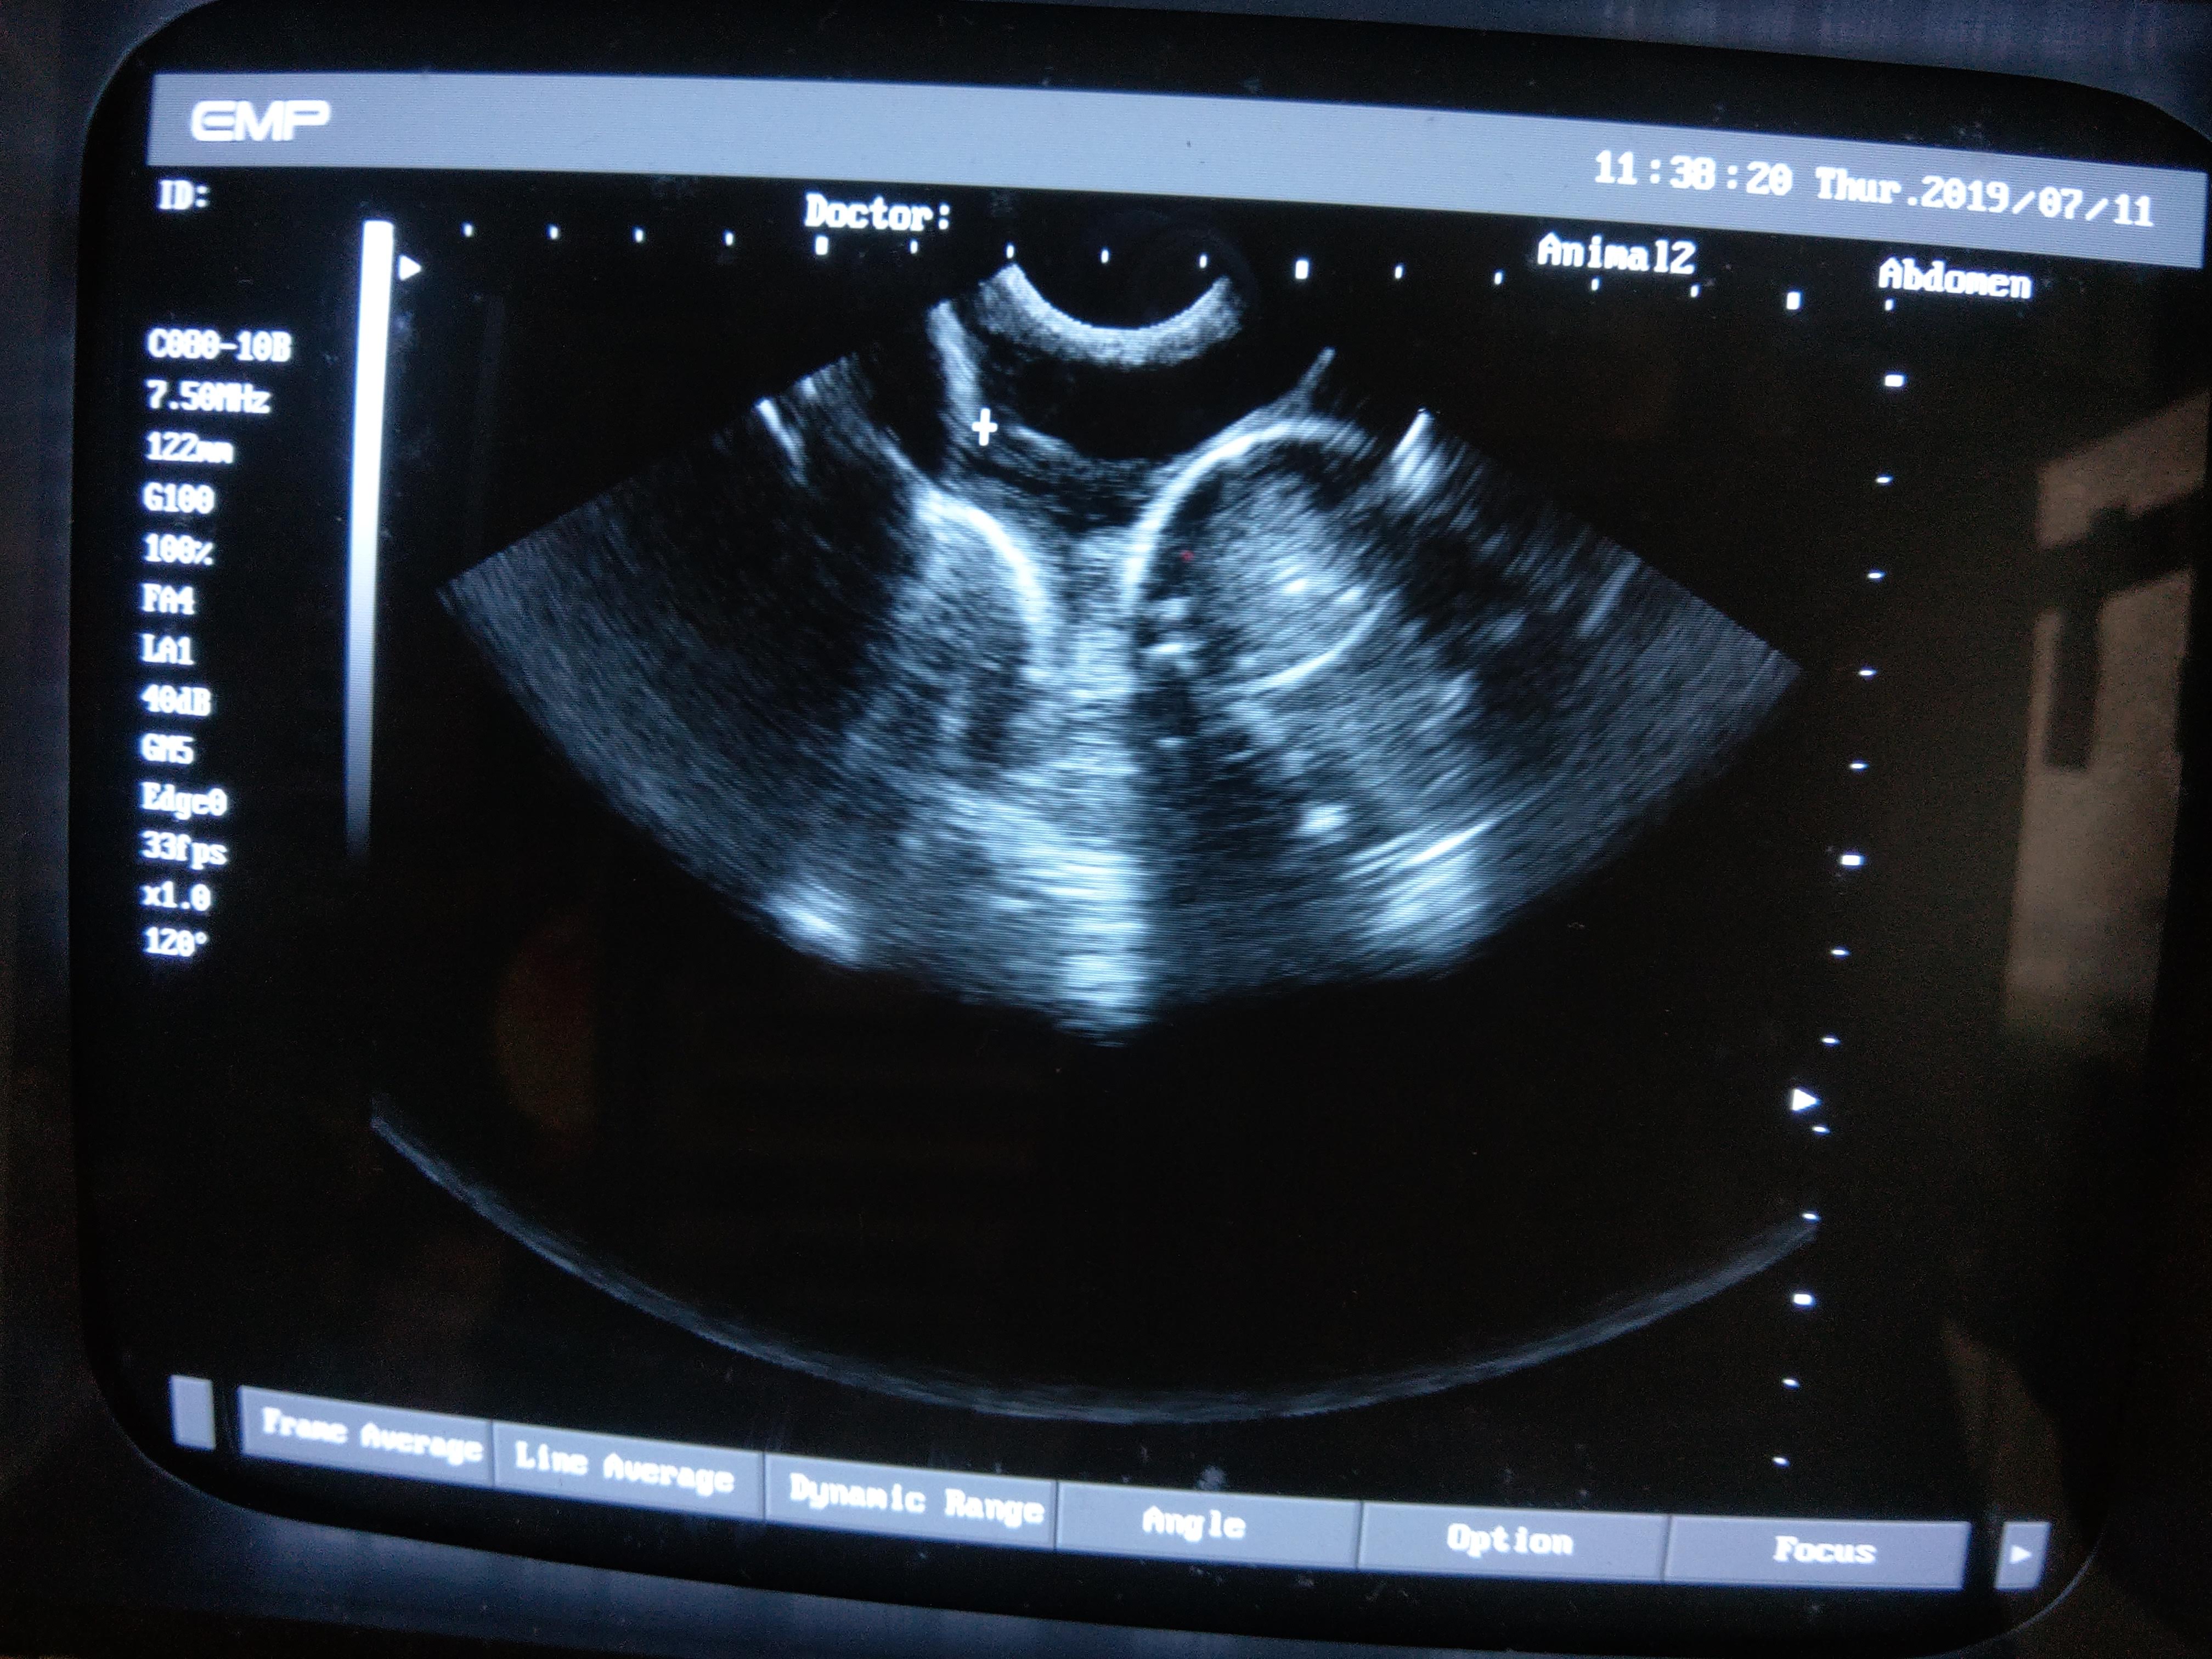

以下是一些記錄照片,有啲圓型冇白邊相信係母龜體內的卵泡,還未完成製蛋過程,還需一段時間才會生蛋。而有白邊的相信是蛋殼的鈣質,體內的蛋已經成熟,隨時準備好產蛋。如果發現有些母龜的蛋在體內己經成熟一段長時間又沒有產下來,就要查證是否有塞蛋等問題。